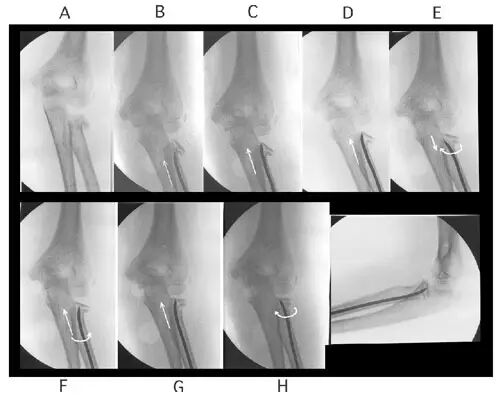

详细图解如下:

ESIN 复位骨折而且稳定骨折

Metaizeau技术

可以单独使用 也可结合经皮撬拨技术与闭合复位的方法联合运用。